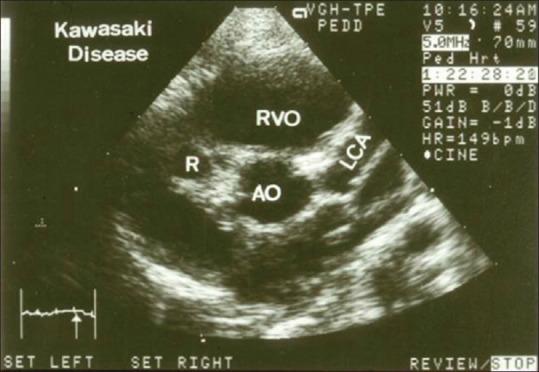

Kawasaki disease (KD) is an etiology-unknown but with a generalized inflammatory disorder of multiple organs and systems in childhood. The basic pathologic changes are panvasculitis of the small and medium-sized arteries, mainly the coronary arteries. It is now the leading cause of acquired heart disease during childhood in developed countries and has led to the early development of angina pectoris, myocardial ischemia/infarction, and even sudden cardiac death in early adulthood. Although there is no definitive diagnostic test for KD, the accurate diagnosis is dependent on the clinical presentations to meet the diagnostic criteria. Echocardiography is a well-known noninvasive tool to detect structural abnormalities and evaluation of cardiovascular function. It has been reported to detect accurately the early and late cardiovascular abnormalities, including perivascular brightness, lack of tapering, dilatation, and aneurysmal formation of coronary arteries as well as the mitral/aortic regurgitation, pericardial effusion, and myocardial functional changes in KD. In cases of incomplete form of KD and patients whose clinical manifestations did not meet the diagnostic criteria, abnormal echocardiographic findings of coronary artery may provide the assistance for early diagnosis of KD. Long-term periodic echocardiographic follow-up is the basic and essential study for patients of KD with initial coronary arterial abnormalities. Ninety nine articles that studied echocardiographic findings of KD had been reviewed and will be discussed.

川崎病(KD)是一种病因不明的儿童期多器官和系统的全身性炎症性疾病。基本病理变化是中小动脉的全血管炎,主要是冠状动脉。它现已成为发达国家儿童后天性心脏病的主要原因,并导致成年早期心绞痛、心肌缺血/梗死,甚至心源性猝死的早期发生。虽然目前尚无针对KD的确切诊断试验,但准确诊断依赖于临床表现符合诊断标准。超声心动图是一种众所周知的用于检测结构异常和评估心血管功能的非侵入性工具。据报道,它能准确检测KD早期和晚期的心血管异常,包括血管周围亮度、缺乏逐渐变细、扩张以及冠状动脉瘤形成,还有二尖瓣/主动脉反流、心包积液和心肌功能变化。在不完全型KD病例以及临床表现不符合诊断标准的患者中,冠状动脉超声心动图异常表现可为KD的早期诊断提供帮助。长期定期的超声心动图随访是初始冠状动脉异常的KD患者的基础且必要的检查。已对99篇研究KD超声心动图表现的文章进行了综述并将予以讨论。